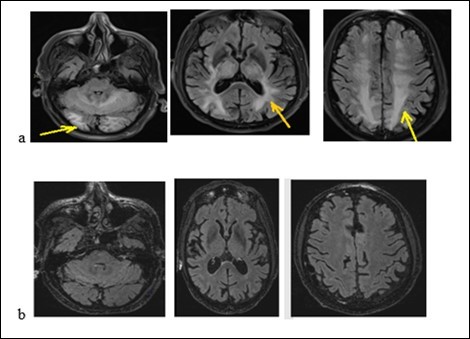

An old man of 74 called J. R. was admitted to hospital on January 26, 2018 for generalized tonic-clonic seizures. The symptoms began 2 weeks before his admission by abdominal pain, vomiting, diarrhea without fever. They were followed by generalized tonic-clonic seizures. According to his medical history, he suffers from high blood pressure, non-insulin-dependent diabetes, chronic obstructive pulmonary disease (COPD), moderate renal failure on a single kidney. He underwent a left nephrectomy for a papillary urothelial tumor, a right upper pulmonary lobectomy for the removal of a bronchial adenocarcinoma. He has been treated with Gemcitabine (Gemzar) and by Fluorine uracil (Folfox) for a pancreatic adenocarcinoma. He also has 3 adrenal nodules. The physical examination noted drowsiness but the patient was reactive to minor stimuli with a Glasgow score of 13/15, a flaccid right hemiplegia. We noted that there was not a neck thifness. Besides, the blood pressure was 210/95 mm Hg and the heart rhythm was regular without heart murmur or additional noises. The rest of the physical examination was normal. The biological check-up had shown a creatinine level at 203 micromol/l with a clearance at 29.9 ml/min, a hyperkalaemia at 6 mmol/l and a hypercalcemia at 2.62 mmol/l. The CSF study had shown a hyperproteinorachy at 0.940g / l, a glycorachy at 5.6 g/l, the CSF count cell displayed 6 cells/mm3 without germ. The brain MRI (Figure 4a) had displayed on flair sequences, diffuse and symmetrical hyper signals of the sub-cortical white matter of the temporal, occipital, frontal lobe and the cerebellum. These radiological findings evoked a RPE syndrome. The treatment included hyperhydration and an anti-epileptic drug. The outcome was noticeable with the decrease of symptoms. We relied on the diagnosis of RPE syndrome. The brain MRI checking-up (Figure 4b) at 40 days was displaying a complete decrease of the lesions.

Figure 4.Brain MRI with flair sequences showing hyper signals of white matter and cerebellum corresponding to edema (a) and the decrease of lesions after treatment (b).